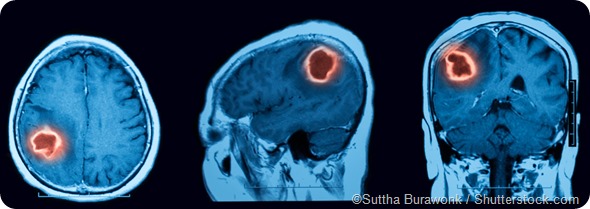

Intracerebral hemorrhage (ICH) is a type of stroke caused by sudden bleeding in the brain. Only approximately 15% of strokes are due to ICH, but it is one of the most disabling types of strokes to suffer from, with a high rate of morbidity and mortality. Roughly one third of patients experiencing ICH will not survive, and only 20% regain their independence and function.